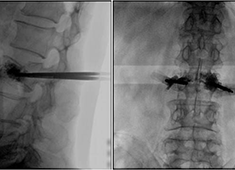

C臂機在打骨水泥時是怎么使用的(PKP手術記錄)

在打骨水泥時通常要借助C臂機來進行,具體是如何使用的呢?下面通過南京醫科大學第二附屬醫院的一則手術案例來深入學習。首先將患者處于俯臥位,然后利用普愛大平板C臂機擺位靈活的特點,快速定位椎弓根位置...